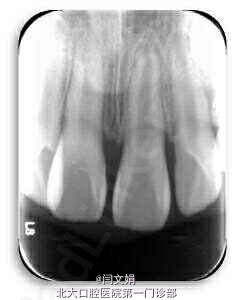

11挫入,切缘位于龈上约2mm,x线示牙根发育形成约二分之一